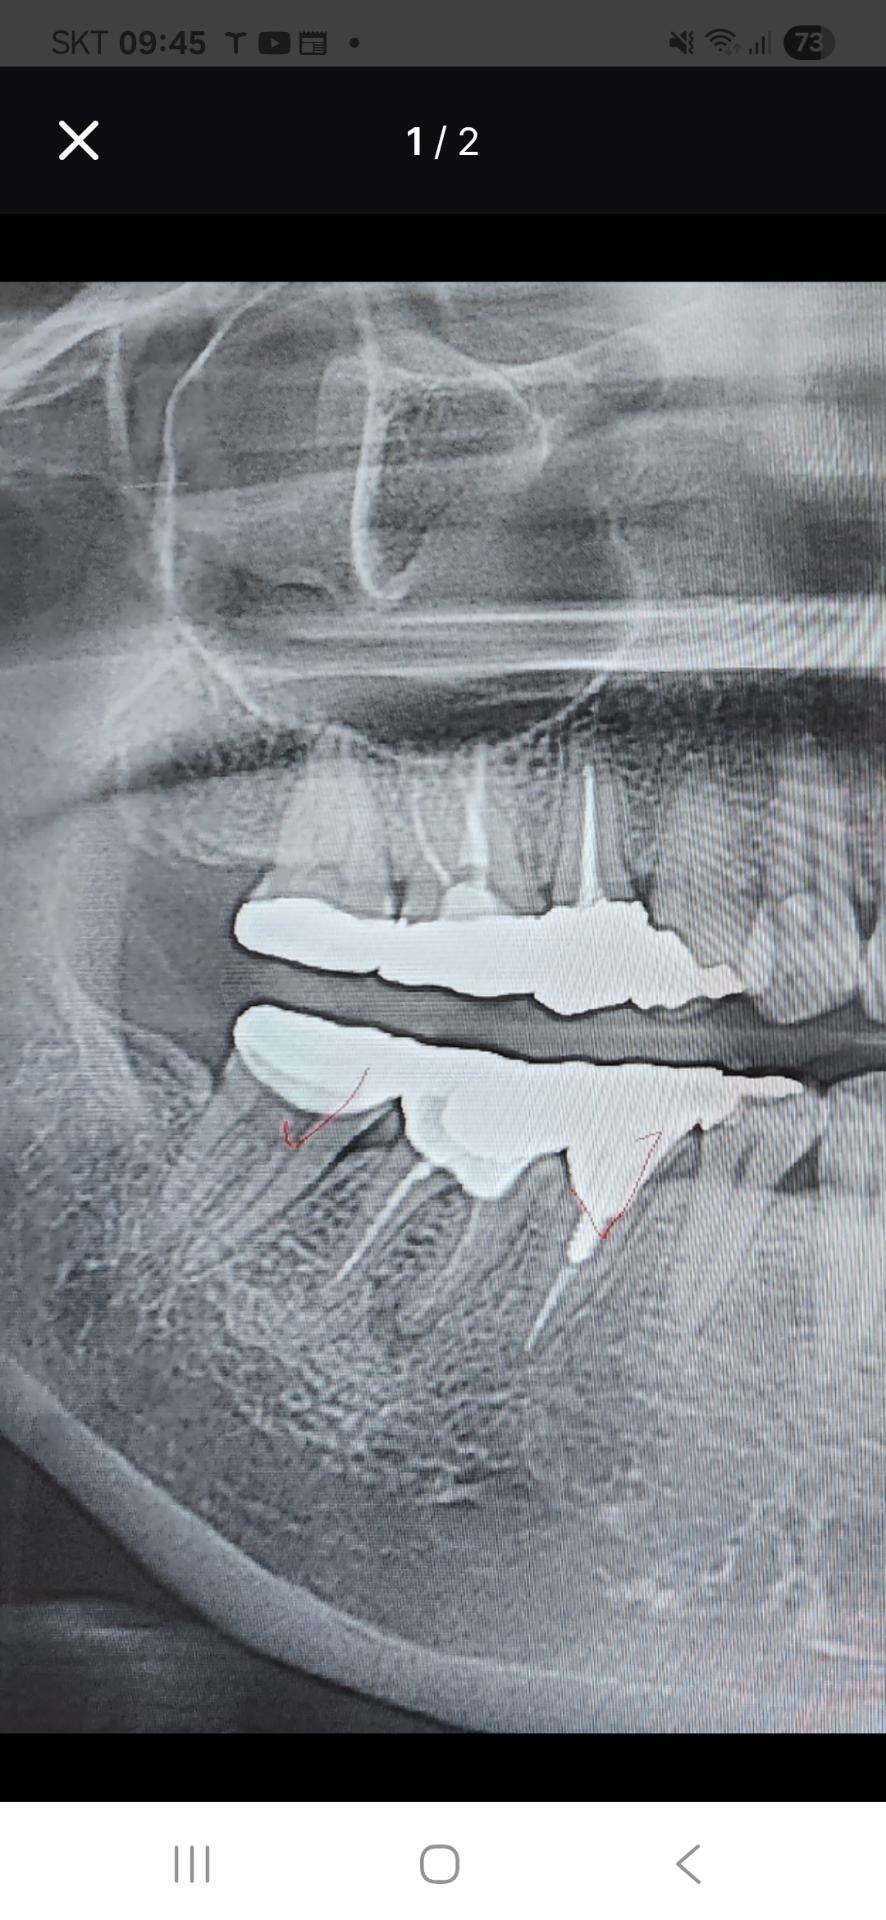

치아 뿌리 염증이 심해진건가요?선생님들 알려주세요

2년전부터 자주 붓는 편이고 아프거나 하진 않습니다 치근단 수술 하면 더 사용 가능한건지 궁금해서요 2년전에 크라운 교체했는데 치아내부가 좋진 않아서 재신경치료는 하지 않았고 치근단절제술을 마지막으로 해볼수 있지 않을까 하는데 붓는거 빼고는 통증은 별로 없습니다 신경치료 흔적?같은거 일수도 있다고 해서 안심했었는데 약간 커진것 같아요 그냥 둬도 될까요?

엑스레이 상으로는 치아 뿌리끝에 염증이 더 진행되고 잇는거 같습니다. 증상이 없다면 일단은 조심히 사용하시는게 좋을것같습니다.

쓸때까지 쓰는 것도 한가지 방법입니다 어금니라 치근단절제술이 쉽지는 않고요

염증은 있는 상태이나 팔로업이 되어야 커지는 상태인지 나아지고 있는지 체크가 됩니다